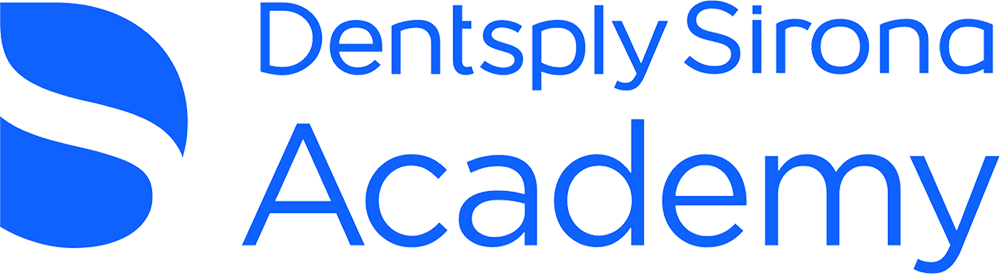

Fig. 1: Mandibular position with condyles seated in the fossae and no intercuspation.

Fig. 5: Occlusion represented as mandibular position and intercuspation.